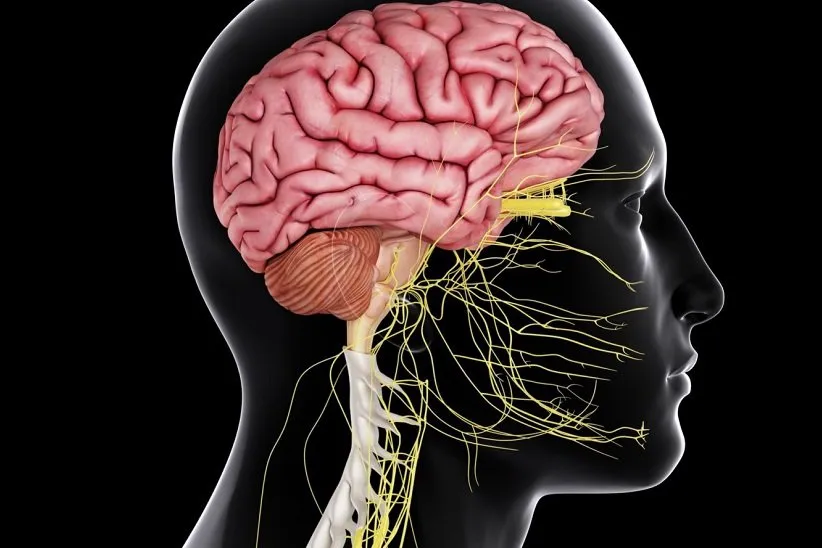

سیستم گلیمفاتیک چیست؟

«سیستم گلیمفاتیک» (Glymphatic System) به سیستم شریانهای خونی در بدن اشاره دارد که سموم و مواد زائد را از مغز و سیستم عصبی مرکزی دفع میکنند. سیستم گلیمفاتیک بیشتر در هنگام خواب فعال است، به همین دلیل داشتن استراحت کافی شبانه برای سلامت ذهن و روان بسیار ضروری است.

سیستم سمزدایی مغز چگونه کار میکند؟

این سیستم به مایع مغزی-نخاعی (CSF) بستگی دارد که وارد فضاهای کنار شریانهای خونی منتهی به مغز میشود. مایع مغزی-نخاعی با مایع بینابینی مبادله میشود؛ مایعی که سلولهای مغزی را احاطه میکند. این به تشکیل سیستم گلیمفاتیک منجر میشود که با جمعآوری سموم و مواد زائد از جمله متابولیتها و پروتئینهایی مانند «آمیلوئید بتا» که در بیماری آلزایمر نقش دارد، مغز را سمزدایی میکند.

در ادامه، این سیستم مواد زائد را از مغز خارج کرده، در بدن منتقل میکند تا در نهایت آنها را دفع کند. در حالی که خواب هستید، به دلیل گسترش فضای میان مایعهای بینابینی و مغزی-نخاعی، فعالیت سیستم گلیمفاتیک افزایش پیدا میکند. با توجه به برخی پژوهشها، ورزش کردن هم میتواند فعالیت این سیستم را افزایش دهد.

گفته میشود هنگامی که در سیستم گلیمفاتیک اختلال رخ دهد، این میتواند برخی بیماریهای مغزی و مشکلاتی مانند مه مغزی و ضعیف شدن حافظه را در پی داشته باشد. پژوهشگران بر این باورند که داشتن یک سیستم پاکسازی سالم در سیستم عصبی، برای سلامتی مغز و پیشگیری از مشکلات خطرناکِ عصبی مانند آلزایمر، پارکینسون، بیماری هانتینگتون و اسکلروز جانبی آمیوتروفیک بسیار حیاتی است.